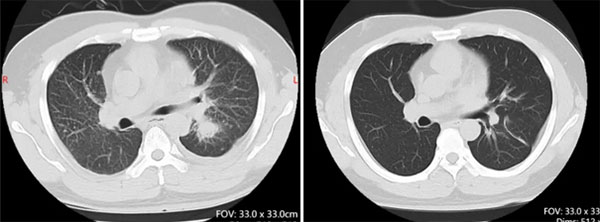

这一发现不仅为患者找到了全新的治疗方向,也填补了ALK罕见突变谱的空白。治疗团队经过充分的文献调研和多学科讨论后,决定给予患者ALK抑制剂阿来替尼靶向治疗。仅仅一个月后,复查胸部CT显示左肺上叶病灶较前明显缩小,疗效评估达到部分缓解(PR),患者的咳嗽、胸闷等症状完全消失,也摆脱了化疗带来的严重不良反应。

靶向治疗前左肺下叶肿块25mm;靶向治疗后左肺下叶肿块5mm